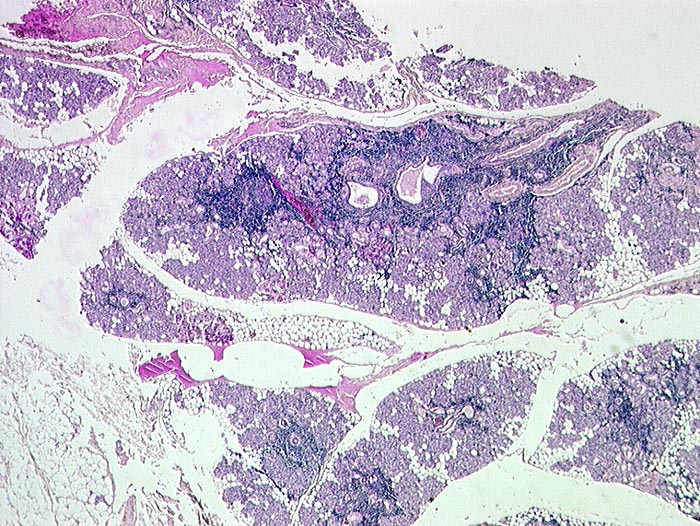

PathoPic ID 120 - Sjögren Syndrom, Parotis

Sjögren Syndrom, Parotis

Entzündung / Reparatur

Parotis

Kopf & Hals, Sinnesorgane

Sjögren Syndrom: St.n. Enukleation des linken Auges wegen spontaner Ruptur. St.n. Hornhautulzera.

Histologie

79